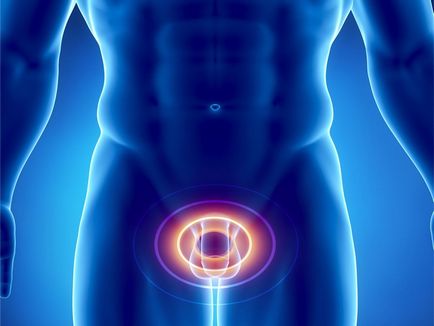

Як відомо, органи сечостатевої системи мають велику кількість кровоносних судин і дуже добре кровоснабжаются. Внаслідок різних патологічних станів в малому тазі може виникати венозний застій в сечостатевому венозній сплетінні. В результаті такого застою розвиваються дегенеративні зміни в органах статевої системи, що призводять до порушень репродуктивної та сексуальної функцій, а також до розладів сечовипускання. Такий стан організму називається конгестівних хворобою, і дуже часто захворювання зустрічається саме у представників чоловічої статі.

Під впливом перерахованих вище етіологічних факторів в малому тазу відбуваються функціональні зміни, судини мочеполового сплетення розширюються, в органах малого таза сповільнюється кровотік, досить великий обсяг крові вимикається з циркуляції. В подальшому розвивається дистрофія і склероз стінок венозних судин сечостатевого венозного сплетіння, в результаті чого в органах малого таза виникають стійкі застійні явища. Процеси мікроциркуляції і транскапиллярного обміну погіршуються, створюються сприятливі умови для затримки інфекції і розвитку флебітів і тромбофлебіту, розвиваються конгестівних патології статевих органів, на тлі яких досить часто виникають запальні процеси. Венозний застій в сечостатевому венозній сплетенні може призводити до дуже серйозних і небезпечних ускладнень.

У клінічній картині венозного застою в органах малого таза у чоловіків переважають больовий і дизурический синдром, а також порушення роботи статевих органів. Симптоматика залежить від того, в яких органах малого таза застійні явища виражені більшою мірою. Біль при венозному застої в малому тазу виникає в промежині, в паху, над лобком, в яєчках, придатках, сечівнику і інших структурах малого таза. Біль носить розлитої і ниючий характер, посилюється після тривалого сидіння або знаходження у вертикальному положенні. Дизурические прояви виникають у вигляді никтурии, поллакіуріі, відчуття переповненого сечового міхура. Крім того, пацієнти скаржаться на зниження лібідо, прискорене сім'явиверження, мляву еякуляцію, а також на спонтанні та іноді хворобливі ерекції, які зникають після спорожнення сечового міхура або прямої кишки. Поява подібних симптомів може говорити про розвиток венозного застою в малому тазі.